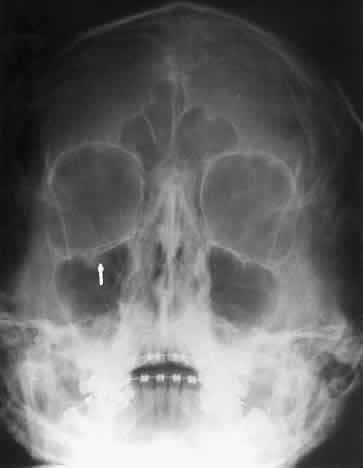

The orbital floor consists of the maxillary, zygomatic, and palatine bones. The floor is thinnest medial to the infraorbital canal, which is the location of most orbital floor fractures (Fig. 7). As mentioned earlier, the floor slopes upward from the lateral to the medial wall. The floor extends toward the orbital apex but does not reach the apex. This orientation of the floor makes frontal projections more informative than the lateral projection.

Fig. 7. A patient involved in a motor vehicle accident who sustained a right orbital floor fracture. Soft tissue density (arrow) located in the roof of the maxillary sinus. Disruption of the orbital floor is seen at the fracture site.

Waters view gives the best image of the anterior and middle portion of the floor. This is possible because extension of the neck brings the floor into a position that is tangential to the x-ray beam. The floor is represented by the most inferior radiopaque line, whereas the orbital rim will be the line above it.10 The vertical distance between these lines should be approximately 1 cm.19 This relationship between the floor and the orbital rim should be symmetric between the two orbits. Any asymmetry should suggest a fracture of the orbital rim or floor.